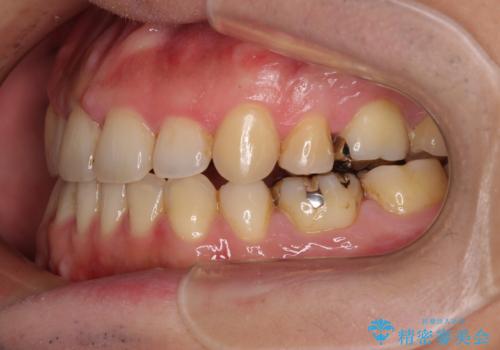

インビザラインの特性を活用して奥歯の咬み合わせを圧下させることで、前歯のオープンバイトを改善さえることができました。

- 抜歯矯正の後戻りを気にして来院された患者様です。

舌の突出癖によるオープンバイトになり、前歯の叢生が後戻りしていました。